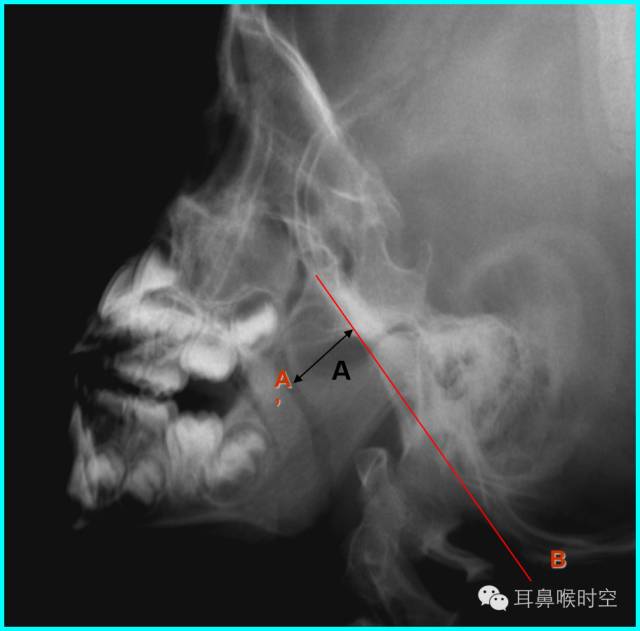

鼻咽侧位片的测量方法(一)

腺样体厚度(A)的测量:

测量:腺样体最突点至枕骨斜坡颅骨外侧面的垂直距离为腺样体厚度:

意义:>13mm,就会出现鼻咽腔气道变窄,甚至闭塞。

鼻咽侧位片的测量方法(二)

腺样体-鼻咽腔比率A/N值:

(1)1987年Elwany提出鼻咽腔的宽度(N)测量方法:

硬腭后端至翼板与颅底交点间的距离为鼻咽腔的宽度。

(2)现多用的鼻咽腔的宽度(N)测量方法:

N为腺样体最凸部鼻咽腔的宽度,即垂线的反向延长线与硬腭后端或软腭前中部上缘的交点和枕骨斜坡颅外面切线的垂直距离。

鼻咽侧位片的测量方法(三)

鼻咽后气道宽度(PAS)

PAS宽度:软腭表面与腺样体表面最凸点之间有效气道宽度(图中a’)

鼻咽口气道宽度是鼻咽最小气道宽度

PSA宽度参考值:

PAS标准:

≧10mm:属正常范围.

6~10mm:视腺样体生理性或中度肥大,

≤5mm:可认为腺样体重度肥大。

≤3mm:患儿多有张口呼吸.

文献报道认为:当A/N值≥0.71,PAS≤3mm,可作为手术指征。